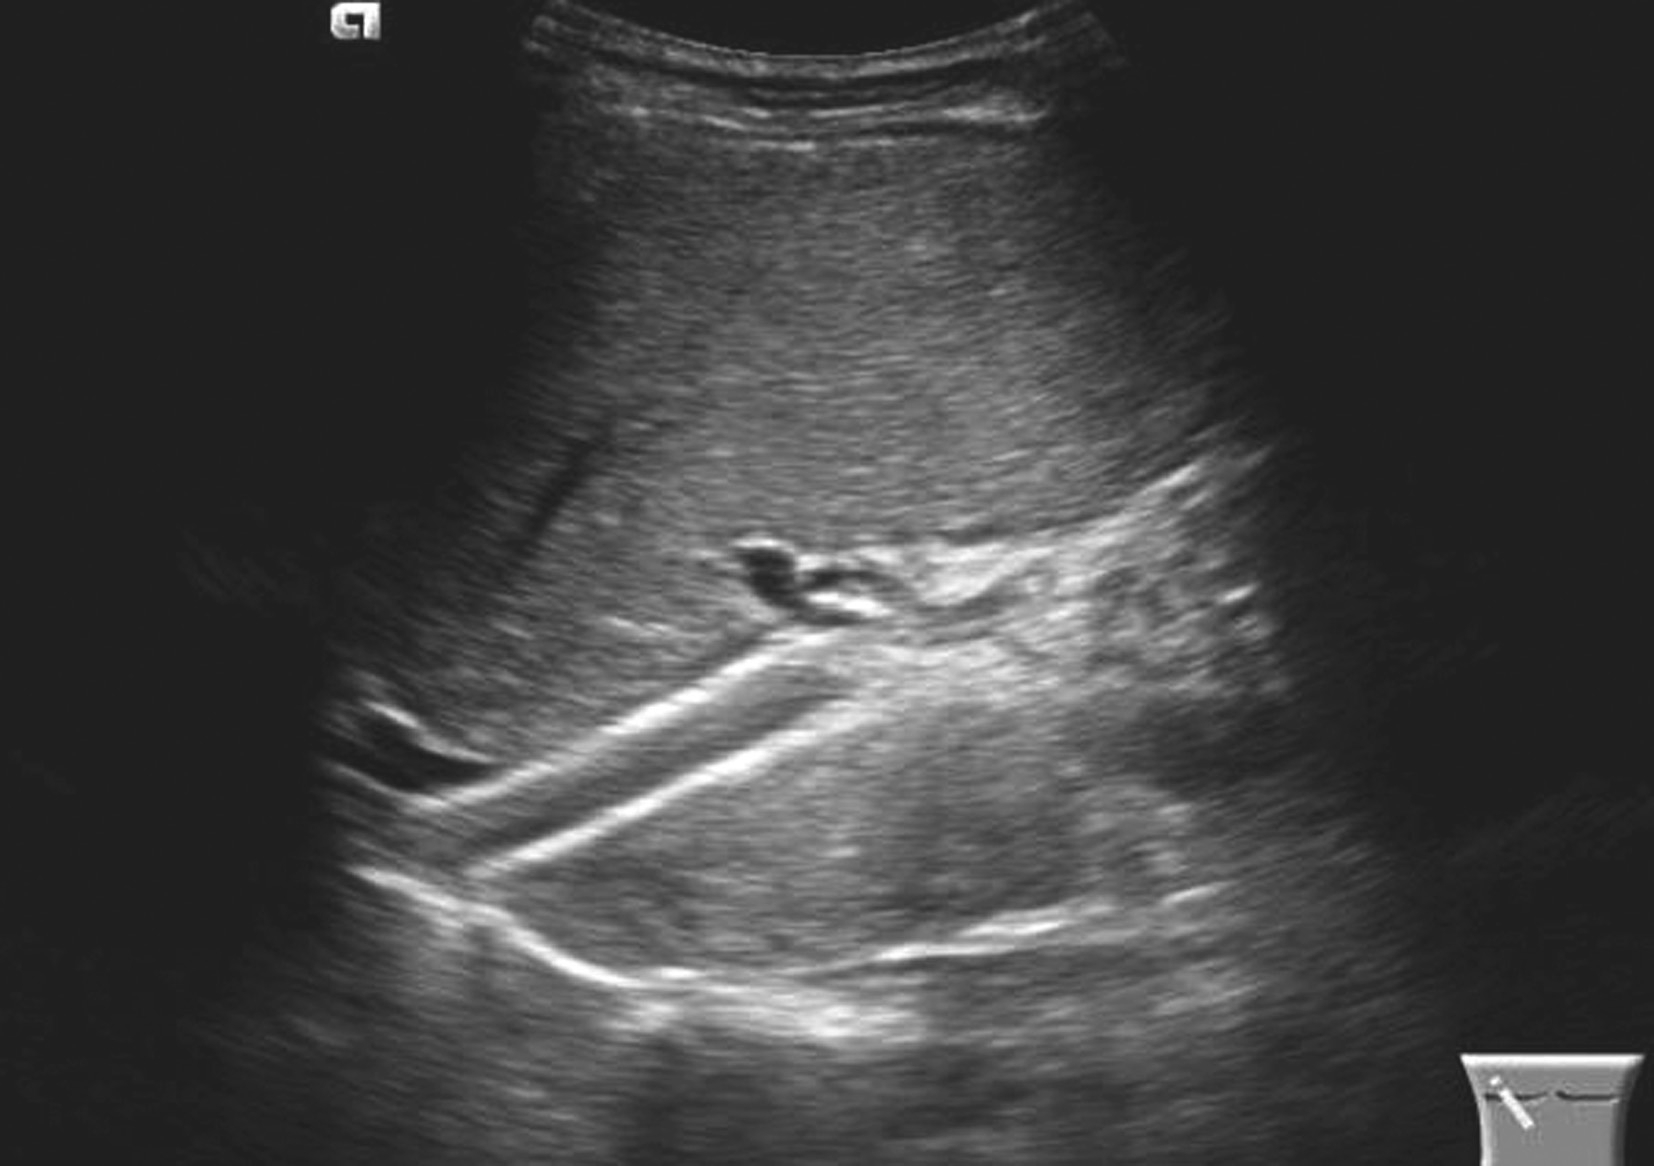

(2)下腔静脉近心段(肝后段)狭窄或闭塞,如图5-21-28所示。表现为局部管腔变细、消失,管腔内有膜性、实质性梗阻物或腔外有肿瘤压迫。肝段或肝后段下腔静脉膜性狭窄者管腔内探及线状低回声隔膜斜行,根据隔膜上有无孔分为膜狭窄型和膜闭塞型,远段下腔静脉及肝静脉扩张。

图5-21-28 原发性BCS:下腔静脉膜性梗阻二维灰阶图像